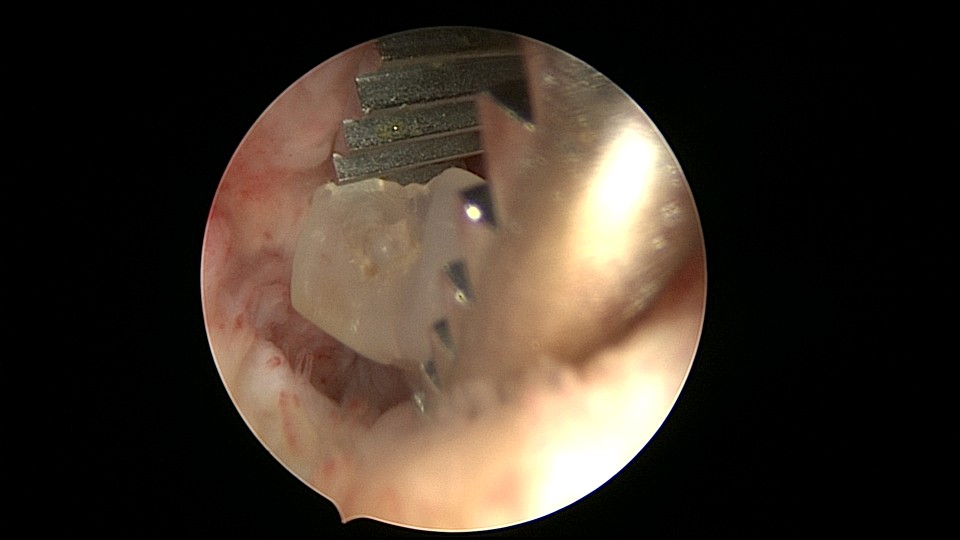

患者51岁,G4P3,顺产3次,闭经半年,外院B超提示有2个环。反复追问病史,还原宫内双环情况,24年前最后一次妊娠可能为带环受孕,行人流术,环未取出(医生和病人不知道有环),随即再次放环一枚。宫腔镜见母体乐环位置下移,纵臂卡在宫颈管内,宫腔镜难以进入宫腔,异物钳先取出母体乐。宫腔内见另一O型环,与右侧宫壁广泛嵌顿,异物钳、取环钩配合中弯钳拉出节育环,环完整,扭曲变形,宫壁见节育环割裂痕迹,宫腔无其他异常。